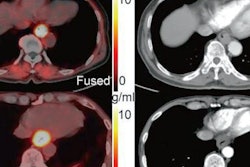

Volunteer patients underwent one whole-body Ga-68 FAPI-46 PET/CT scan (Biograph 64 mCT or Biograph 64 TruePoint, Siemens Healthineers) and subsequently, surgical resection of their primary or metastatic tumor. Lastly, the researchers compared Ga-68 FAPI-46 PET maximum standardized uptake values (SUVmax and SUVmean) with FAP immunohistochemistry scores in cancer and noncancer tissues for each patient.

Image courtesy of the Journal of Nuclear Medicine.They found Ga-68 FAPI-46 SUVs and immunohistochemistry scores were higher in cancer than in normal tissue: mean SUVmax 7.7 vs. 1.6 (p < 0.001), mean SUVmean 6.2 vs. 1.0 (p < 0.001) and mean FAP immunohistochemistry score 2.8 vs. 0.9 (p < 0.001). In addition, FAP immunohistochemistry scores strongly correlated with Ga-68 FAPI-46 SUVmax (r = 0.781) and SUVmean (r = 0.783) across all cancer types.